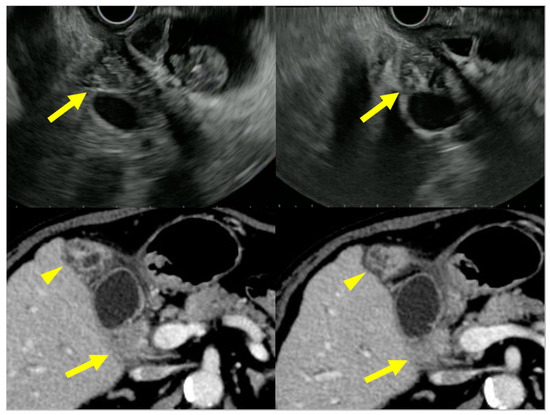

4.1. Diffuse Type of IgG4-CC

4.2. Localized Type of IgG4-CC